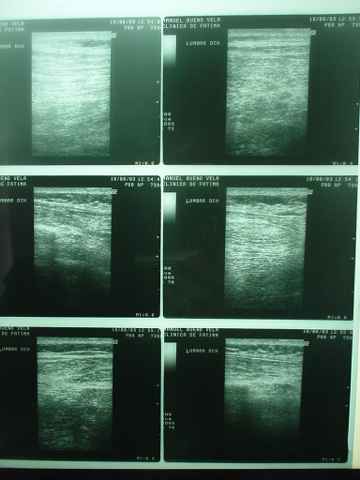

Le apreciamos posible cornada cerrada en la zona lumbar dcha; contusión

intensa en zona interna de tercio medio de muslo Izquierdo, posible afectación

osea de costilla flotante inferior dcha.y contusiones y erosiones diversas.

Inmovilizamos la que hallmos como lesión principal: la lesión

muscular lumbar.

Y además cerciorarnos que el riñón y zonas adyacentes

están preservados, para lo cual de inmediato se le practica TAC lumbar,

Sedimento urinario y radiología de parrilla costal.